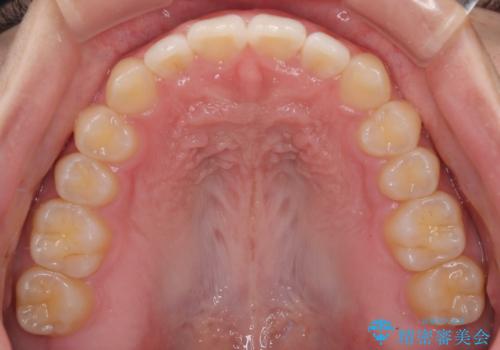

- 「前歯のすきっ歯が気になる」「食べ物が歯の間に詰まりやすい」とのお悩みで来院された20代男性の患者様です。

歯と歯の間に隙間がある**空隙歯列(すきっ歯)**は、見た目の問題だけでなく、食片圧入による歯肉の腫れや、隣接面う蝕のリスク増加につながることがあります。

診査により舌突出癖が認められました。この癖は、すきっ歯の原因となるだけでなく、矯正後の後戻りリスクを高めます。